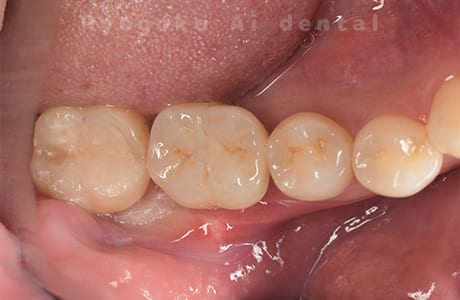

Case07

- 原因

- 右下6番歯根破折

-

- 治療内容

- インプラント治療

- 治療費用

- 約600,000円

右下の腫れが治らないとの事でご来院された患者様です。歯が割れていたため、抜歯を行い、骨に代わるお薬を入れ、インプラントを埋入致しました。経過良好で大変満足していただけました。

<リスク・副作用>

治療後、痛みや違和感、出血、腫れなどが出る事があります。喫煙者、糖尿病などの方の場合、歯が生着しない場合があります。